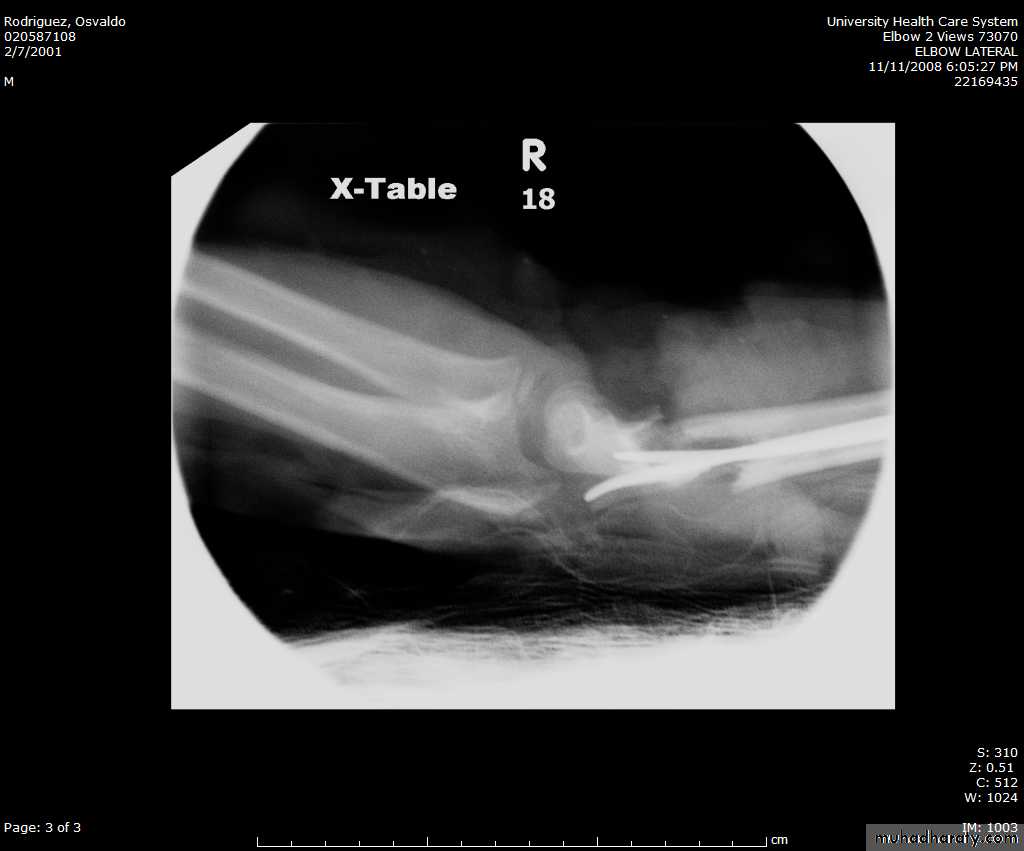

How are we going to stabilize this boy’s fracture?

This is probably one of the few indication to use

Antegrade Flexible I M NailsOur Patient P.O.

Probably acts more

as an internal splintSix months post-operative

How is he doing clinically?